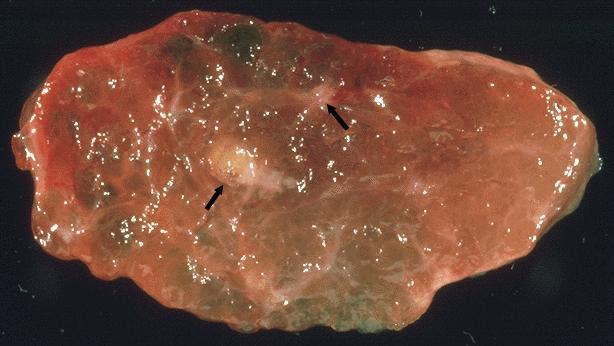

Gross description

- Sporadic: typically presents as a single circumscribed but nonencapsulated, gray-tan mass

- Familial: generally bilateral / multiple foci

- Solid, gray-tan-yellow, firm, may be infiltrative

- Larger lesions have hemorrhage and necrosis, tumor usually in mid or upper portion of gland (with higher density of C cells)

- < 1 cm in size is called microcarcinoma; if < 0.5 cm, associated with a complete absence of clinically detectable metastatic disease (Ann Surg Oncol 2009;16:2875)

Gross images

Contributed by Mark R. Wick, M.D.

AFIP images